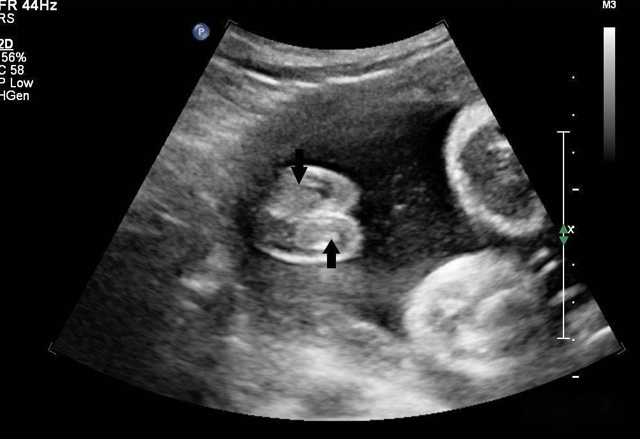

超声波遇见散射体会发生散射强弱大小,形状会周围组织差别、声阻抗很小散射很微弱,形状及周围组织的声阻抗差别相关。血液内尽管含有红白细胞、血小板,普通超声设备没办法显示。人为加入不同介质在血液中增强散射出现雨雾状的回声,这就是超声造影的基本原理。组织对比超声利用了这一原理。静脉注射超声造影剂随着血液灌流而发展或增强器官和组织的成像,为临床诊断提供成像数据基础。